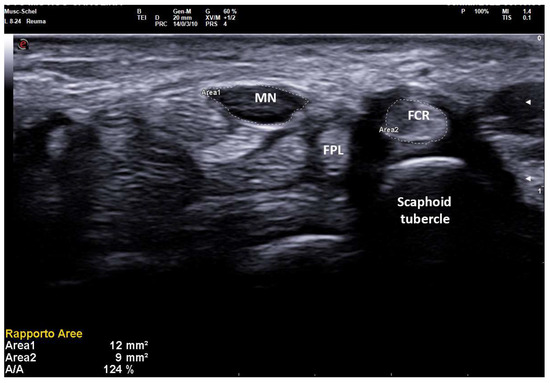

Figure 5. Transverse scan over right carpal tunnel in a small female patient (150 cm × 50 kg, 13.7 cm of wrist circumference) affected with medium-grade CTS (Padua Scale 3, SCV 37.1 m/sec, DML 4.8 ms). Linear 8–24 MHz probe. Both areas of median nerve (MN) and flexor carpi radialis (FCR) were manually traced. A MN-CSA of 12 mm2 is not always considered pathologic (cut-off for MN neuropathy until 14–15 mm2 in some studies on CTS) and the severity is often underestimated because of the anthropometric characteristics of the patient. The NTR shows values unequivocally pathologic (124%), as MN-CSA is compared with an anatomic structure (FCR-CSA) that maintains small dimensions in CTS, following the anthropometric characteristics of the patient.